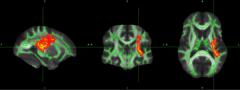

The spectrum, pathophysiology, and recovery trajectory of persistent post-COVID-19 cognitive deficits are unknown, limiting our ability to develop prevention and treatment strategies. We report the one-year cognitive, serum biomarker, and neuroimaging findings from a prospective, national study of cognition in 351 COVID-19 patients who had required hospitalisation, compared to 2,927 normative matched controls. Cognitive deficits were global and associated with elevated brain injury markers, and reduced anterior cingulate cortex volume one year after COVID-19. The severity of the initial infective insult, post-acute psychiatric symptoms, and a history of encephalopathy were associated with greatest deficits. There was strong concordance between subjective and objective cognitive deficits. Longitudinal follow-up in 106 patients demonstrated a trend toward recovery. Together, these findings support the hypothesis that brain injury in moderate to severe COVID-19 may be immune-mediated, and should guide the development of therapeutic strategies.